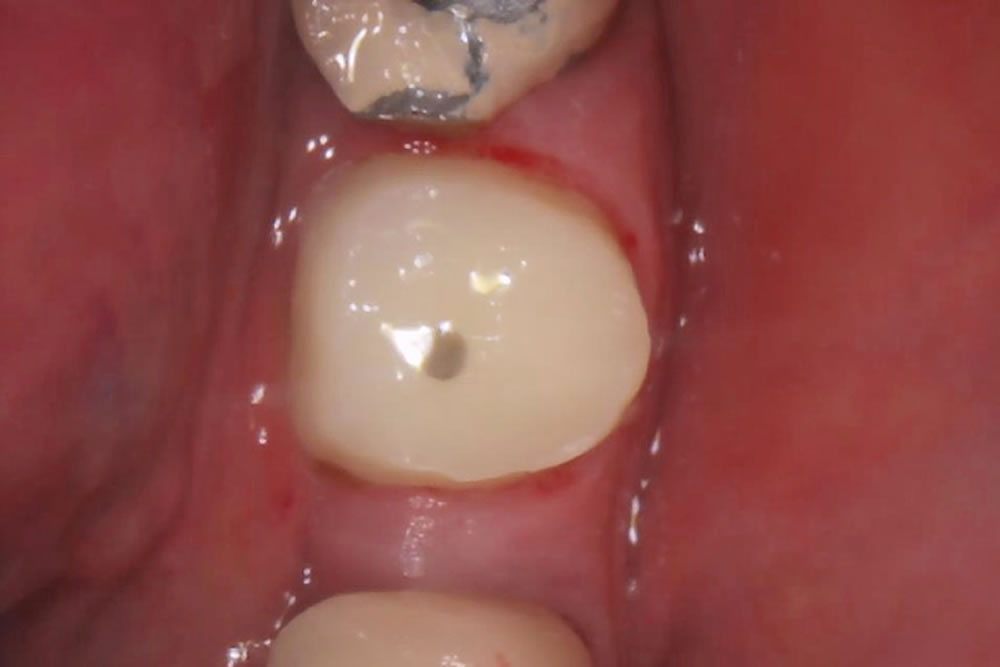

グラスファイバーの軸を挿入し、プラスチックで補強した土台を立てました。

この土台は歯と似た弾力性を持つため噛む力が分散され、歯の根が割れるリスクを減らせます。

また、金属の土台のように黒ずんできたりすることがなく、光を通しやすいため審美性に優れています。